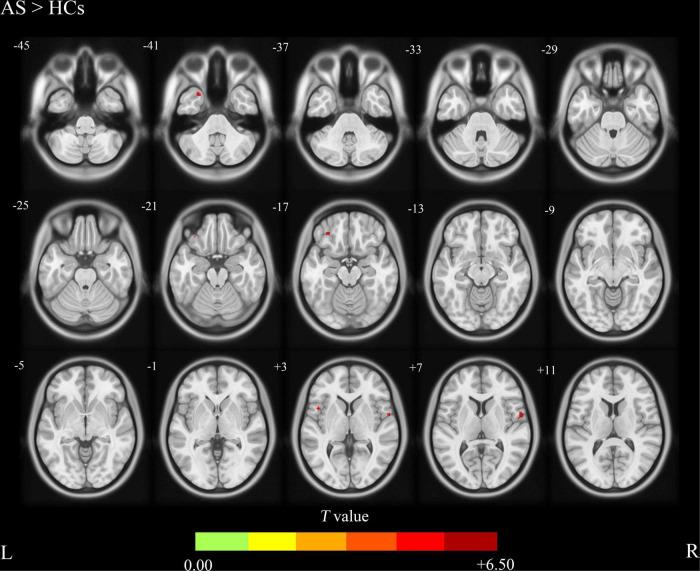

The AS group showed increased CBF values in the right precentral gyrus, the left inferior frontal gyrus, and the left temporal pole compared with HCs the AS group also showed decreased CBF values in the left precuneus and the left superior occipital gyrus compared with HCs. There were no significant correlations between the CBF values and the clinical characteristics including total back pain (TBP), erythrocyte sedimentation rate (ESR), and C-reactive protein (CRP).

与HCs相比,AS组右侧中央前回、左侧额下回和左侧颞极的CBF值升高;与HCs相比,AS组左侧楔前叶和左侧枕上回的CBF值降低。CBF值与包括总背痛(TBP)、红细胞沉降率(ESR)和C反应蛋白(CRP)在内的临床特征之间无显著相关性。